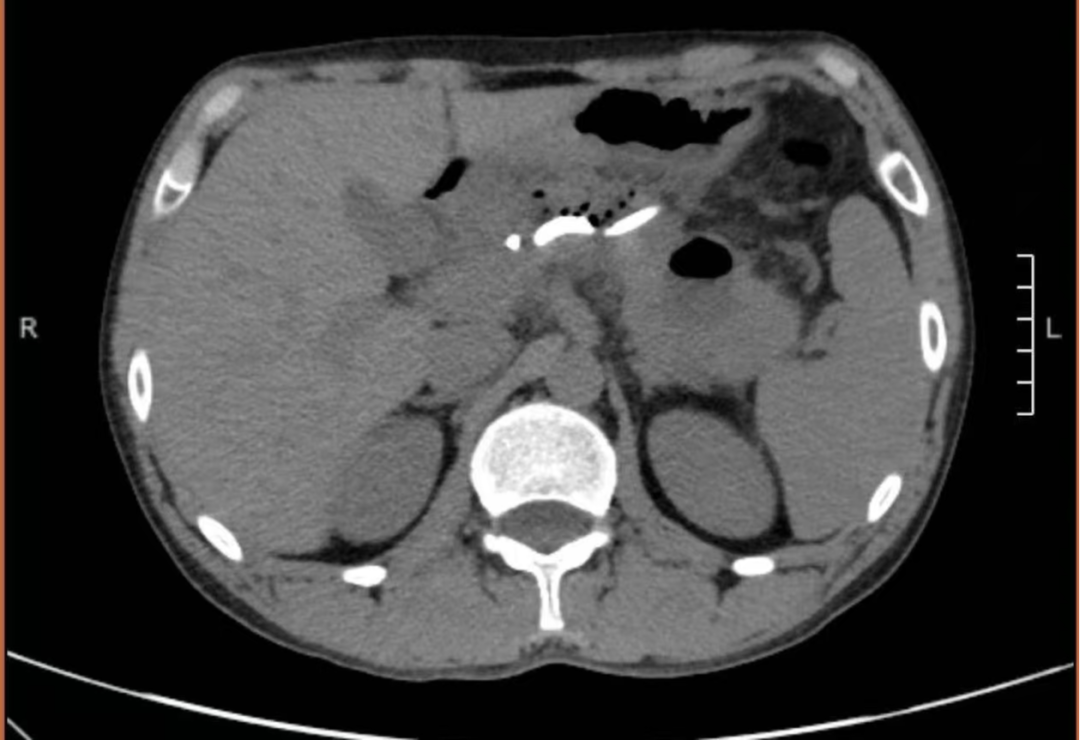

术后患者腹胀、腹痛症状迅速缓解,引流液逐渐清亮。经抗感染与营养支持治疗,患者恢复良好,术后5天顺利康复出院。复查影像显示囊肿基本消失,标志着本次微创治疗取得圆满成功。

患者术后复查CT